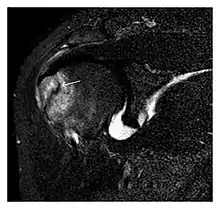

The greater tuberosity of the humerus is also an illustrative location of occult fractures. The osseous injury may follow seizures, glenohumeral dislocation, forced abduction, or direct impaction. They are commonly discovered on MRI in symptomatic patients with suspicion of rotator cuff tear. Coronal images are best suited for detection. They appear as crescentic oblique lines surrounded by a bone marrow edema pattern (Figure 5). The rotator cuff must be inspected since associated ligamentous lesions are common. In the ankle, malleoli and tarsal bones should be checked carefully for any cortical disruptions and radiolucent lines that may reveal a fracture. Awareness of the exact location of the pain will help direct the attention of the interpreter when searching for very subtle signs of fracture (Figure 6).[1]

Figure 5: Traumatic fracture of the greater tuberosity in a 51-year-old man presenting with left shoulder pain after a fall on ice. Initial radiographs were normal. Coronal inversion recovery MRI shows a fracture line (arrow) through the greater tuberosity surrounded by a bone marrow edema pattern.[1]